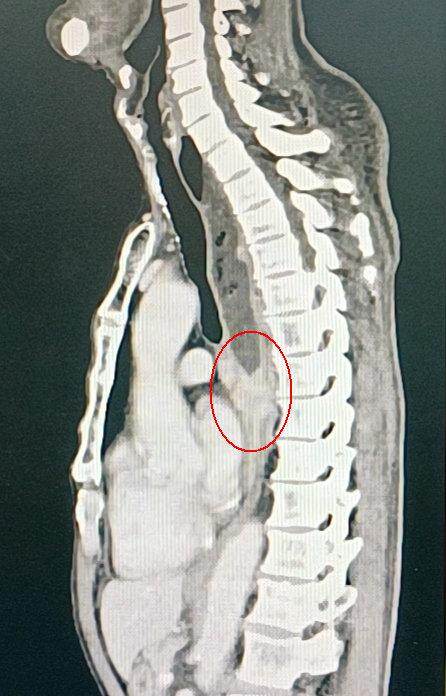

经进一步胃镜检查显示,张伯距鼻缘34-38mm处可见环周生长肿物,表面鱼肉状。病理提示考虑低分化癌。进一步完善全身检查后,未见远处转移,心肺功能良好,有手术指征。该院胸外科张才铭主任了解病情后,食管癌诊断明确。

食管肿瘤大小约6.0×3.0cm,完全堵塞食管

尽管张伯年纪较大,手术风险大,但食管肿瘤已完全堵塞食管,需要进行手术切除。在家属同意下,2020年12月17日,胸外科张才铭团队在麻醉科手术室等科室密切配合下,为张伯进行了胸腹腔镜联合下颈胸腹食管癌根治术。